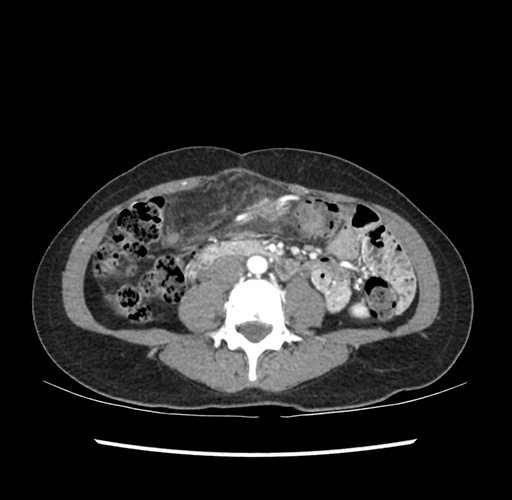

Imaging Analysis

Look through the patient's CT scan to identify any areas of concern for the necessary procedure.

Based on your CT findings, which issue(s) would give reason for "planned slowing down moment(s)" in this case?